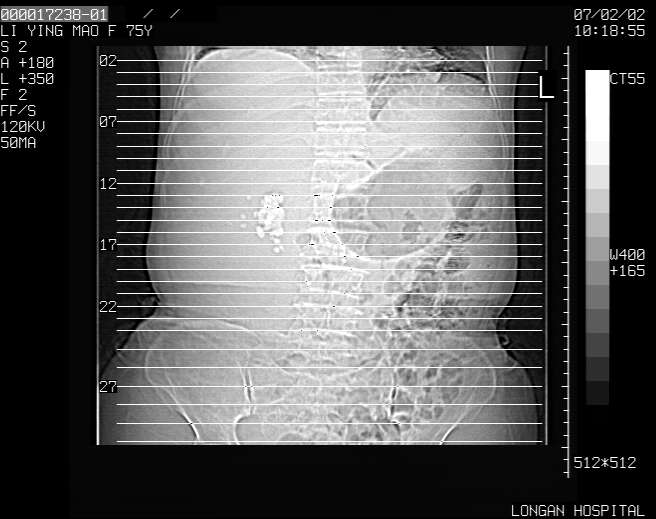

以下是引用dyqct在2007-2-10 8:53:00的发言:[br]考虑:1、肝脏多发囊肿[br] 2、左肾囊肿,右肾多发结石并积水。[br] 3、右胸少量积液。[br] 4、右肾周包裹性积液或淋巴管瘤(有见缝就钻的征象、薄隔、小结节状钙化)?[br] 5、腰椎动脉瘤样骨囊肿?[br] [br] [br]